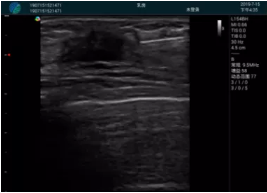

腺體內(nèi)部清晰顯示一低回聲塊影,形態(tài)不規(guī)則,邊界模糊,邊緣呈毛刺狀,內(nèi)部見(jiàn)砂礫樣鈣化

M20引導(dǎo)下穿刺活檢術(shù)

M20引導(dǎo)下平面內(nèi)穿刺取出的腫塊組織

M20查看:囊內(nèi)回聲均勻,邊界清晰,囊壁光滑

M20引導(dǎo)抽吸術(shù)后囊腫消失,原區(qū)域空腔形成,脂肪層與腺體層架構(gòu)發(fā)生改變